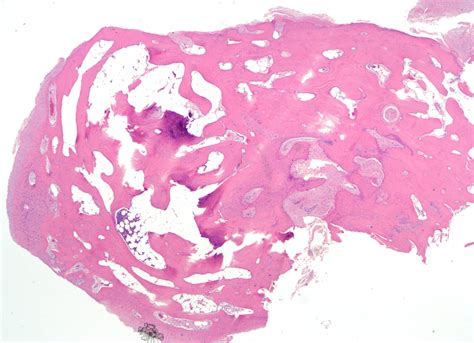

Osteochondral Fragment in the Knee Joint – Prof. Nay Win